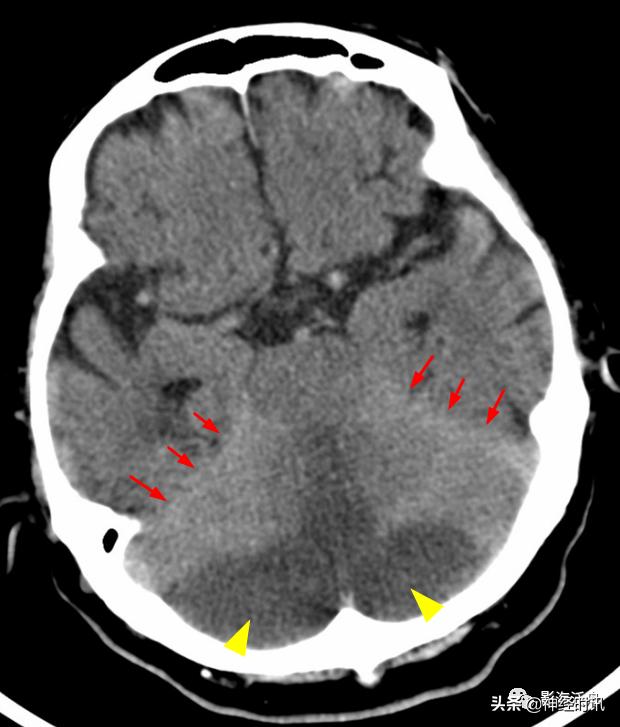

中年女性,骑电动车与人相撞,行头颅CT检查,鞍上池层面可见左侧侧裂池内蛛血(红箭),3天后患者复查头颅CT,左侧侧裂池内蛛血未见明确显示,但同一层面可见右侧天幕区新发蛛血(黄箭)。

通过本病例不难发现少量蛛血的变化是非常迅速的。因此,对于一些可疑的蛛血患者,报告中应建议其短期复查(如24h内)。